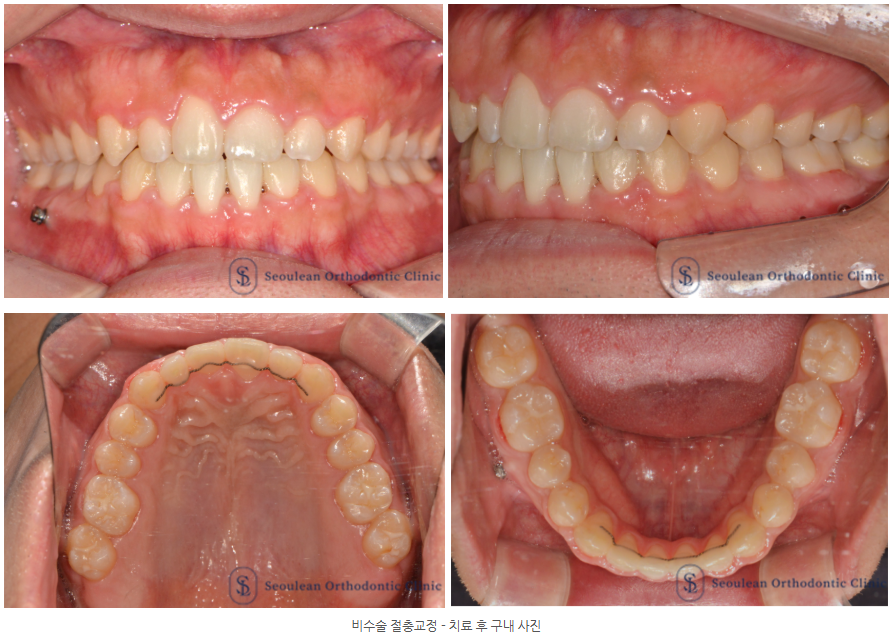

치료 결과 및 평가

약 2년간의 교정치료 후 다음과 같은 변화를 확인할 수 있었습니다.

• 전치부 개방교합 해소

• 반대교합 개선 및 안정적인 전치 교합 형성

• 양측 구치 관계의 기능적 개선

• 중심선 불일치 완화

• 안모 비대칭 감소 및 측모 조화 개선

특히 재발 가능성이 높은 개방교합 케이스에서

근기능치료를 병행했다는 점

치료 결과의 장기적 안정성 측면에서 중요한 의미를 가집니다.